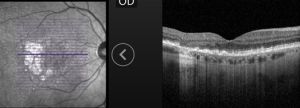

GA is a complex pathophysiologic process that is defined by sharply demarcated atrophic lesions of the outer retina, resulting from the loss of photoreceptors, RPE, and choriocapillaris in the macula.[1] . On fundus evaluation (Figure 1), scalloped areas of hypopigmentation will be found in areas of atrophy with surrounding drusen and pigmentary changes. Fundus autofluorescence (Figure 2) reveals dense hypoautofluorescence due to the lack of lipofuscin following loss of the outer retina and RPE. The amount of perilesional hyperautofluorescence can be used to predict disease progression, with more hyperautofluorescence generally being proportional to the rate of GA growth. Certain patterns of hyperautofluorescence have been implicated in faster disease progression. Optical coherence tomography demonstrates loss of outer retinal layers (outer nuclear layer, ellipsoid zone, interdigitation zone), as well as loss of the underlying RPE and choroidal hypertransmission (Figure 3). In 2017, the Classification of Atrophy Meetings group recommended that non-neovascular AMD trials include color fundus photographs, fundus autofluroescence, near-infrared reflectance, and spectral-domain or swept-source OCT[6], all of which are good tools to help diagnose and monitor disease progression.